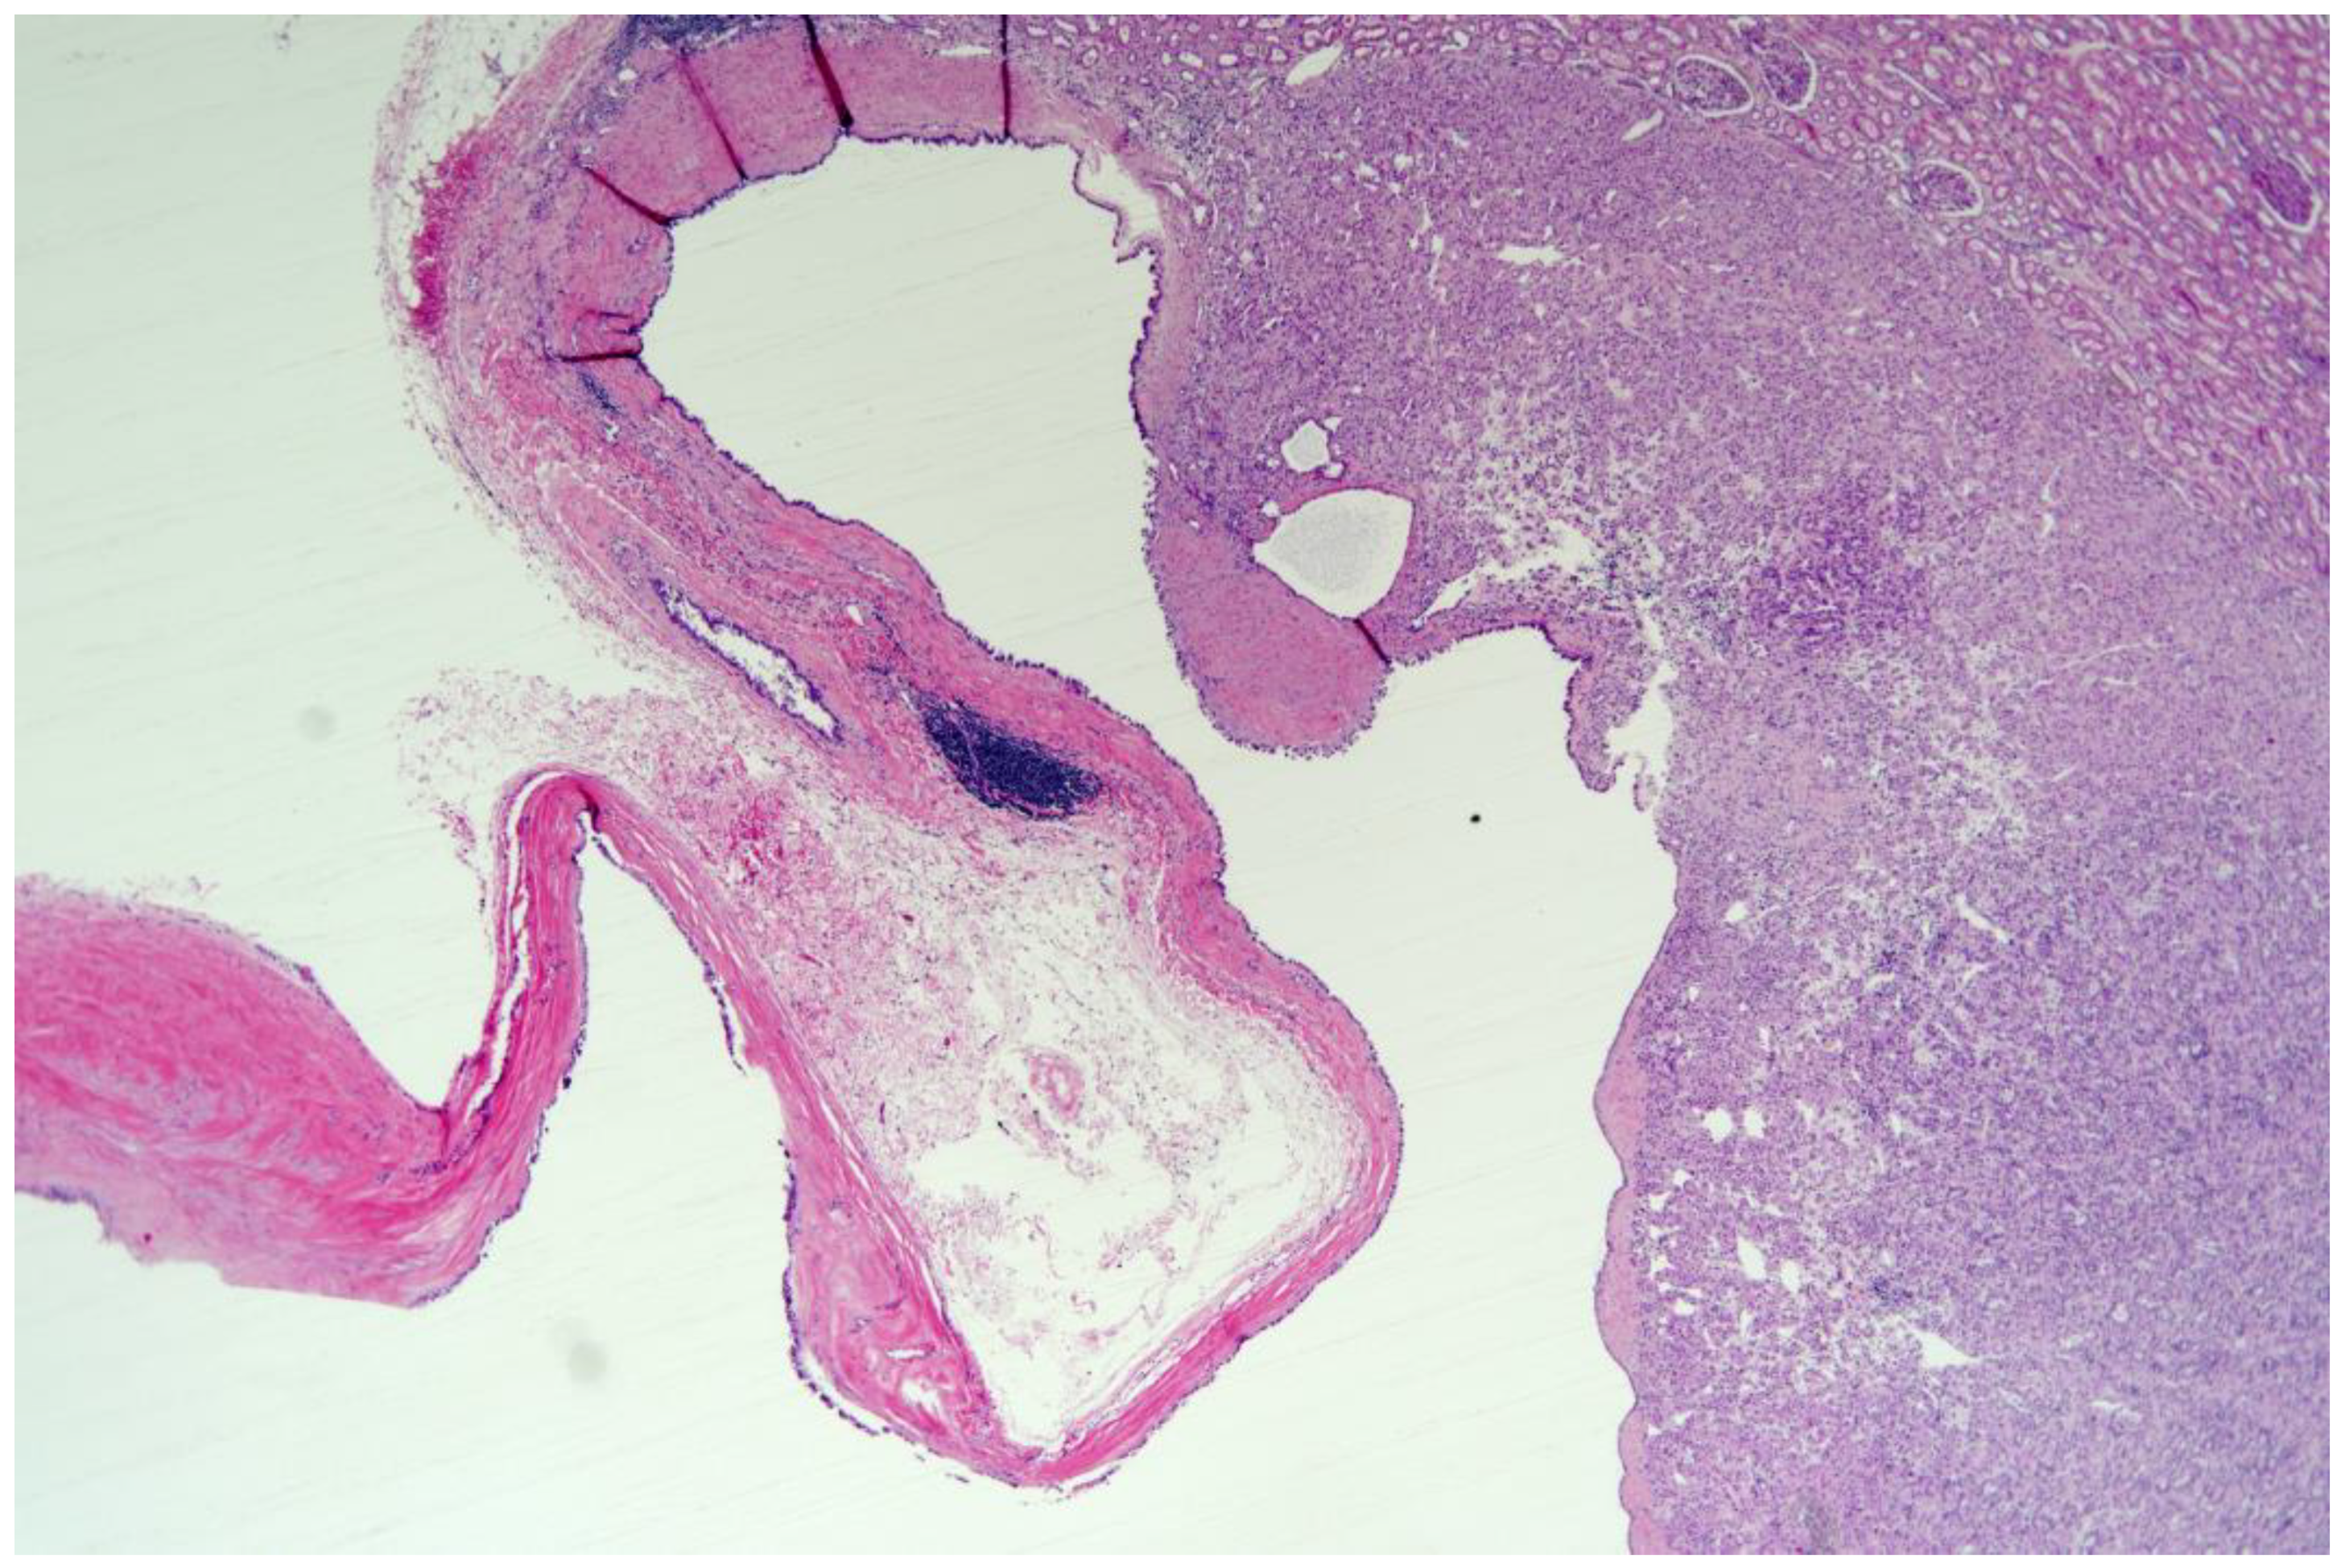

2. Case Report